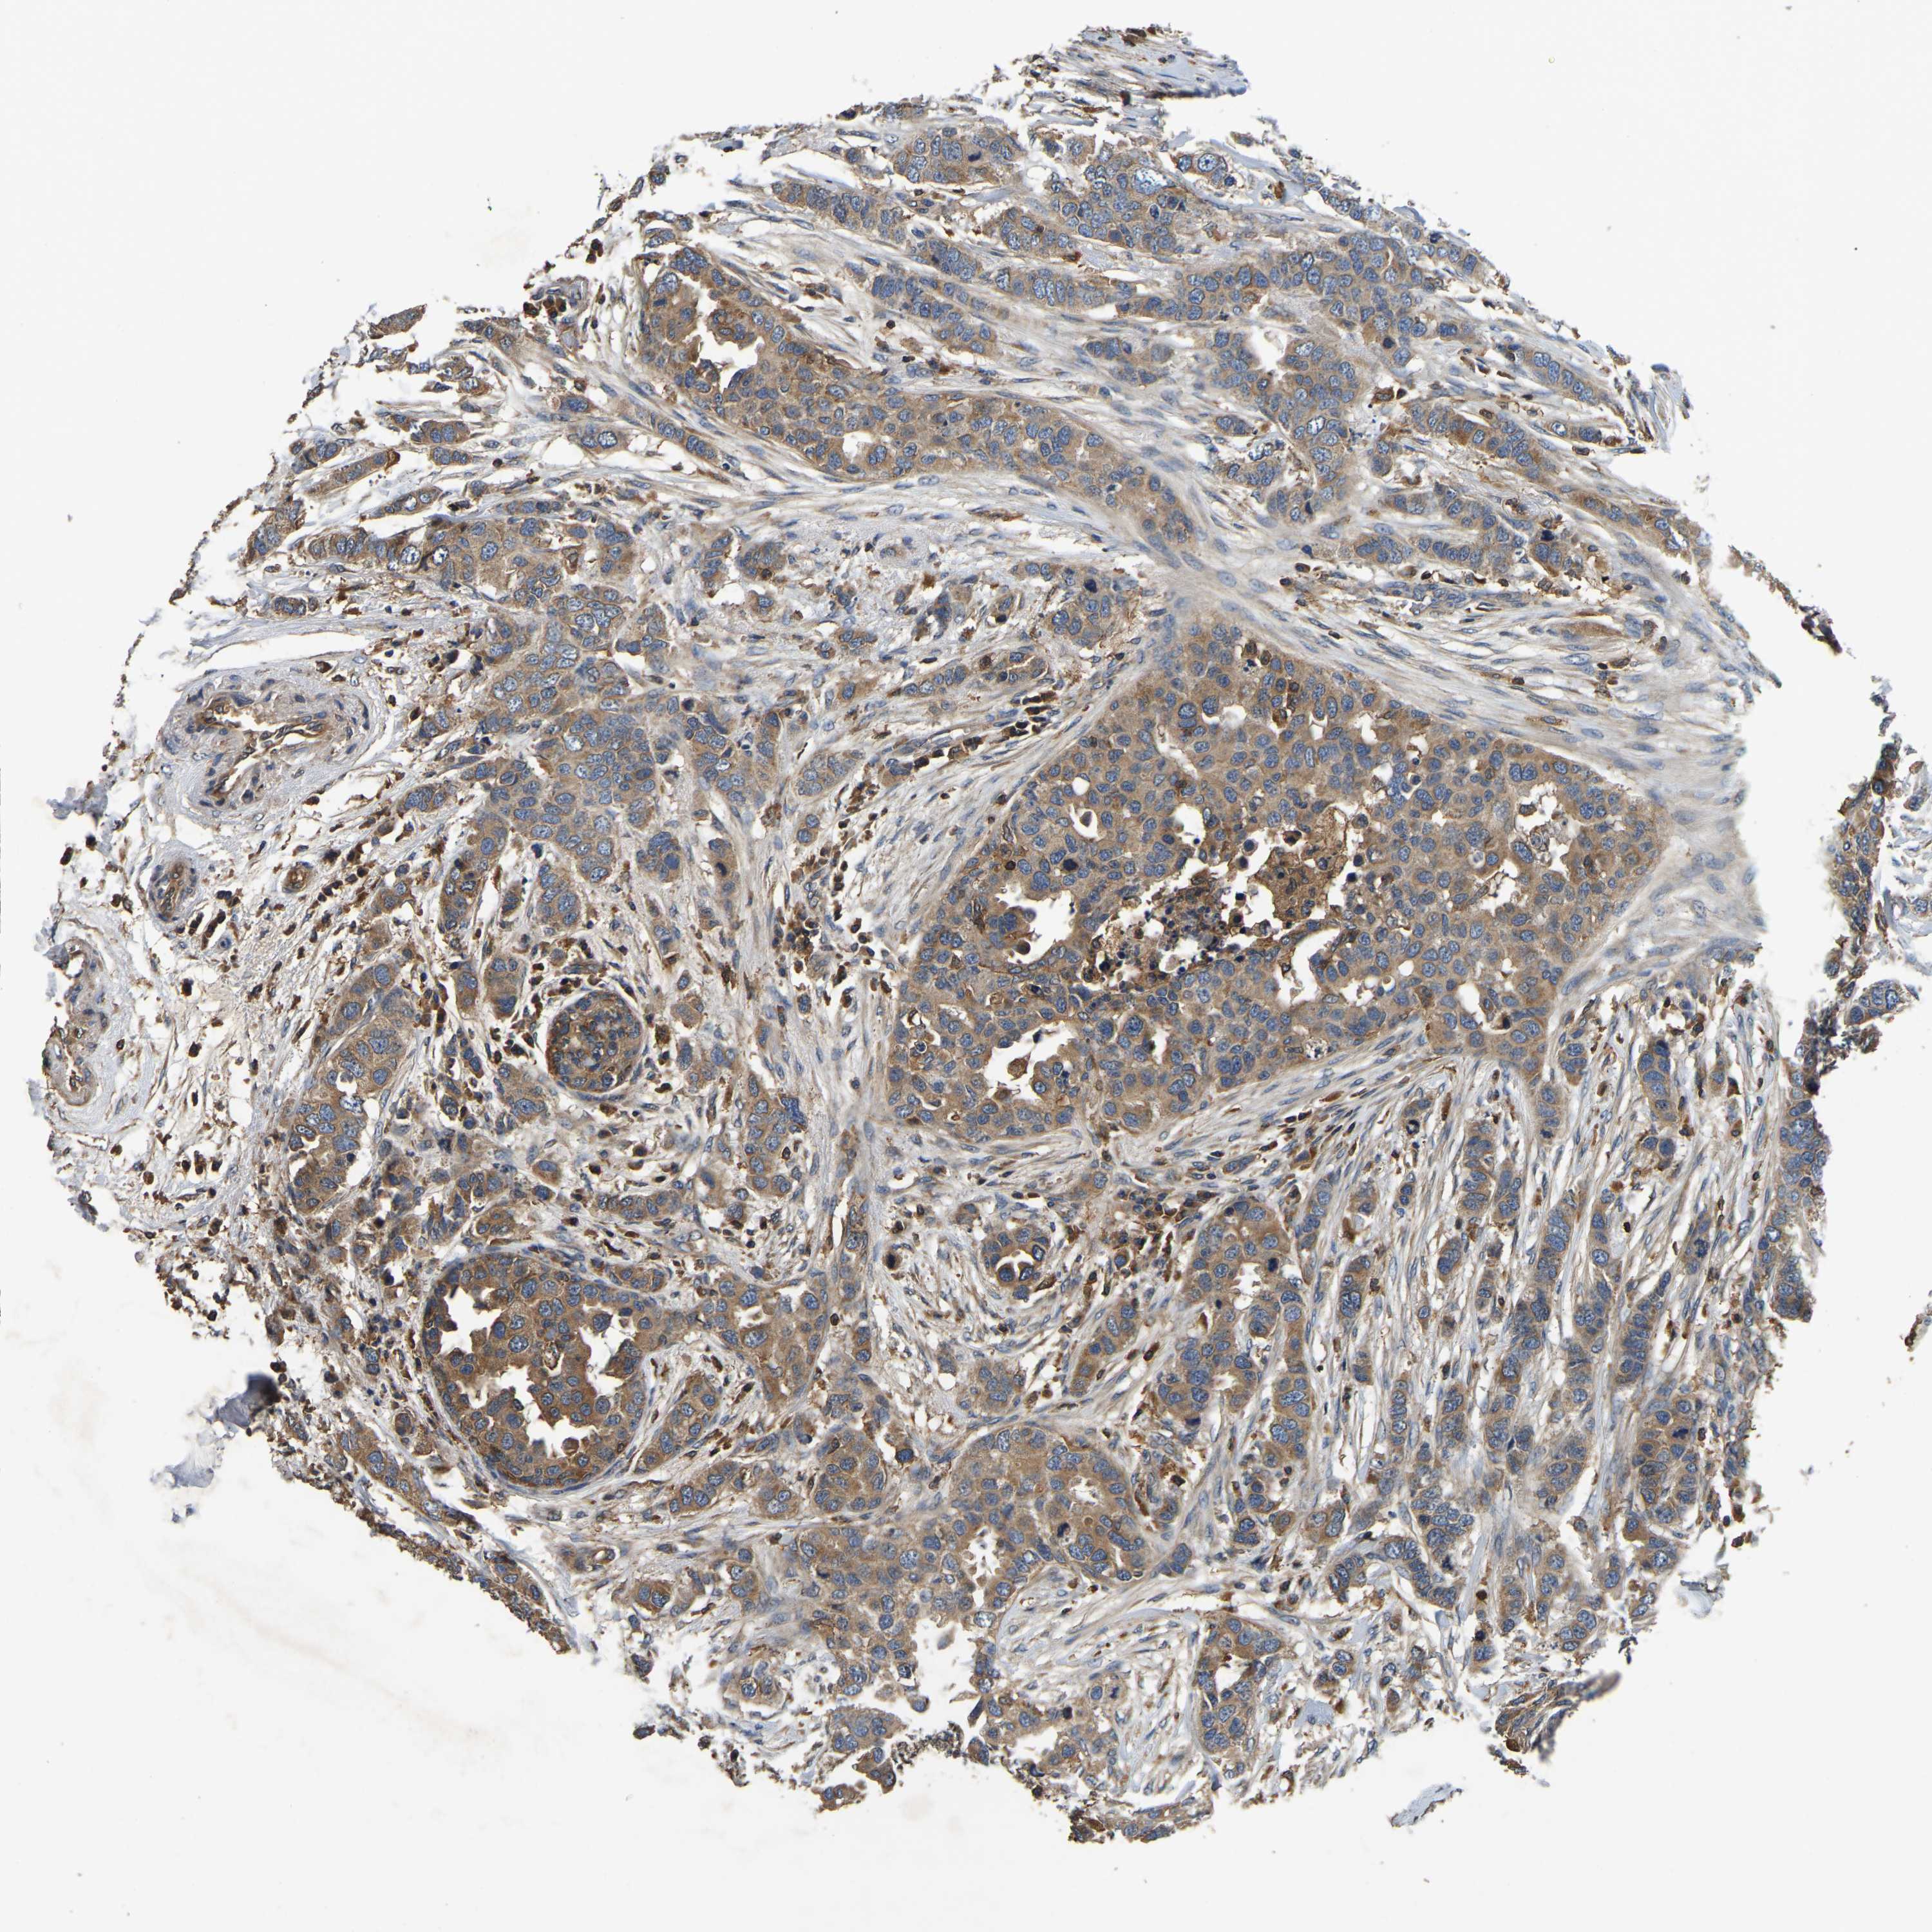

CANCER BREAST CANCER Show tissue menu

BRCA TCGA BRCA VALIDATION PROTEIN EXPRESSION